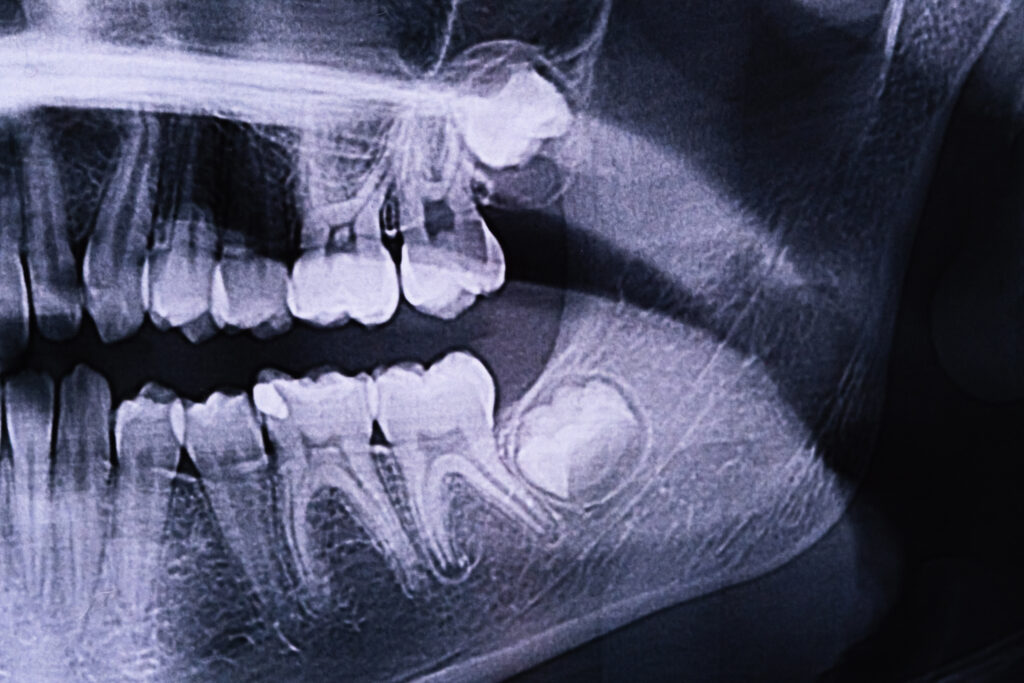

Not all problematic wisdom teeth cause noticeable pain or discomfort right away. Sometimes, issues are hidden beneath the gums, and the first warning sign is visible only on a dental X-ray.

Dentists use panoramic or digital imaging to detect impaction, which occurs when a wisdom tooth is unable to fully erupt due to a lack of space, obstruction by other teeth, or abnormal angulation.

Common types of impaction include:

- Horizontal impaction: The wisdom tooth lies sideways and pushes against the second molar.

- Mesial impaction: The tooth angles forward toward the front of the mouth, pressing on adjacent teeth.

- Vertical impaction: The tooth remains partially trapped in the jawbone, unable to emerge properly.

Even if you don’t feel pain, impacted wisdom teeth can:

- Damage neighbouring teeth by exerting pressure or causing decay

- Create pockets where bacteria accumulate, increasing infection risk

- Contribute to cyst formation in rare cases

Dentists often recommend early extraction of impacted wisdom teeth detected on X-rays to prevent future complications.

Clinical Exam + X-ray (OPG)

Dentists start with a thorough dental examination combined with digital imaging to evaluate:

- Position and angulation of the wisdom teeth

- Bone structure surrounding the teeth

- Relation to critical areas such as the inferior alveolar nerve and maxillary sinus

An orthopantomogram (OPG) X-ray provides a full view of all four wisdom teeth and helps dentists determine whether extraction is necessary and how complex it might be.